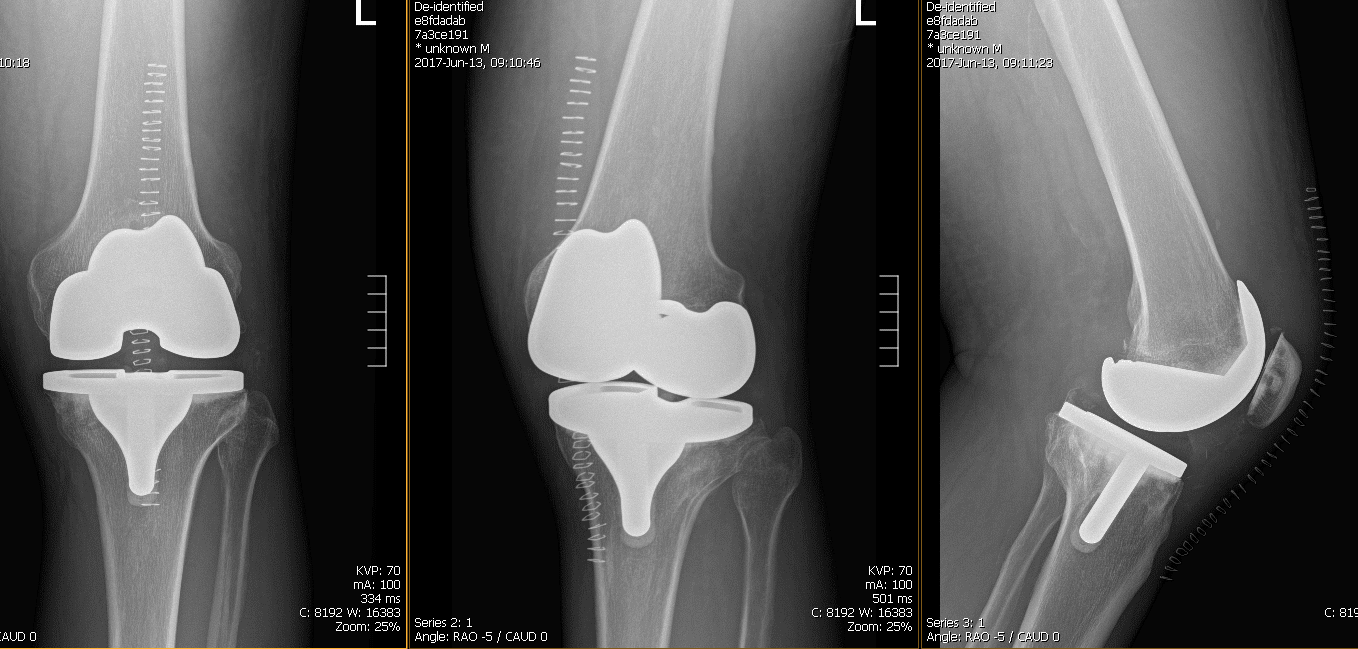

El paciente se sometió a una artroplastia de rodilla total izquierda utilizando un implante personalizado. Durante el procedimiento, su cirujano observó que ya había osteoartritis avanzada. Se utilizó un enfoque parapatelar medial, se colocó la guía de resección tibial tras la exposición de la tibia y se realizó y revisó la resección tibial.

Las radiografías postoperatorias revelaron que el fémur distal, la rótula, la tibia proximal y el peroné proximal muestran márgenes corticales intactos sin fractura aguda. Su herida fue inspeccionada, sin signos claros de infección. Me quitaron las grapas.